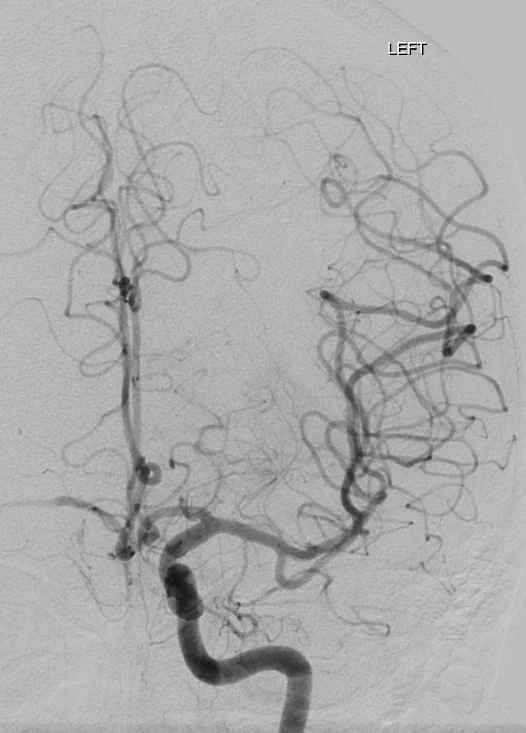

Cet examen invasif, réalisé sous anesthésie locale, permet d’obtenir une analyse morphologique et dynamique très précise des artères et des veines du cerveau ou de la moelle épinière en rendant les vaisseaux sanguins visibles aux rayons X en y injectant un produit de contraste à l’aide d’un tuyau (cathéter) que l’on navigue sous contrôle radiologique depuis le poignet ou le pli inguinal.

L’angiographie cérébrale est un examen diagnostic qui permet de visualiser les vaisseaux qui amènent le sang au cerveau (artères) et ceux qui le ramènent vers le coeur (veines). Les termes artériographie et phlébographie désignent respectivement l’étude spécifique des artères et des veines. Lorsque l’on s’intéresse aux vaisseaux de la moëlle épinière, on parle d’angiographie médullaire.

L’objectif est de rechercher une anomalie des vaisseaux pouvant expliquer vos symptômes. comme une malformation des vaisseaux (anévrysme, malformation artério-veineuse, fistule…), un rétrécissement ou l’occlusion totale d’une artère.

L’examen peut également être réalisé dans le cadre d’un bilan préopératoire afin d’étudier de manière la plus précise possible l’anatomie vasculaire et la vascularisation d’une tumeur par exemple.

Afin d’éviter les infections, le médecin qui pratique l’examen porte une tenue “stérile”. L’équipe paramédicale désinfecte la peau à hauteur du pli de l’aine et/ou du poignet (le plus souvent à droite). On vous recouvre ensuite d’un champ stérile avec un ou des orifices permettant de travailler. Une anesthésie locale est pratiquée en regard de l’artère fémorale ou radiale et un petit tuyau (introducteur) y est placé. Cet accès permet ensuite de coulisser un second tuyau (cathéter) qui sera guidé par le médecin sous contrôle radiologique jusqu’aux artères que l’on souhaite étudier. Plusieurs séries d’images sont alors réalisées en injectant du produit de contraste iodé dans le flux sanguin à l’aide du cathéter et en faisant des radiographies dynamiques de de ce “moulage” des vaisseaux. A chaque injection, vous pouvez ressentir une sensation de chaleur dans la tête, une sensation de vertige, un goût métallique, des scintillements visuels. Ces symptômes durent quelques secondes et disparaissent ensuite complètement.